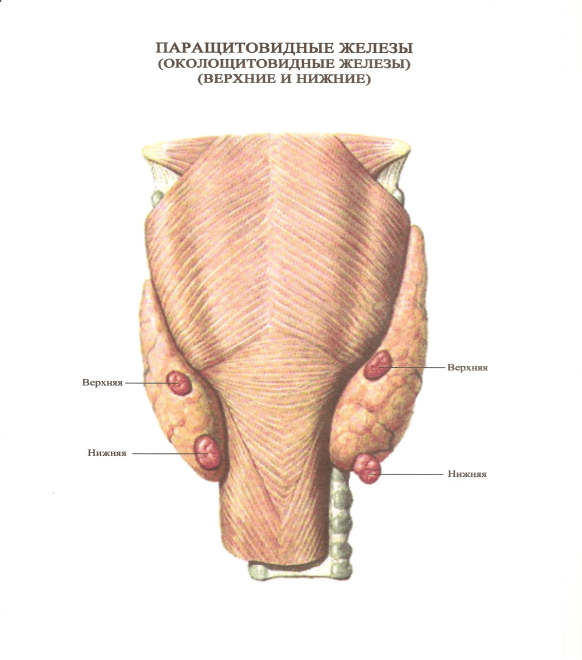

Иллюстрации и схемы по остеопорозу и паращитовидной железе